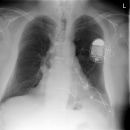

Sunshine C-Pulse Device